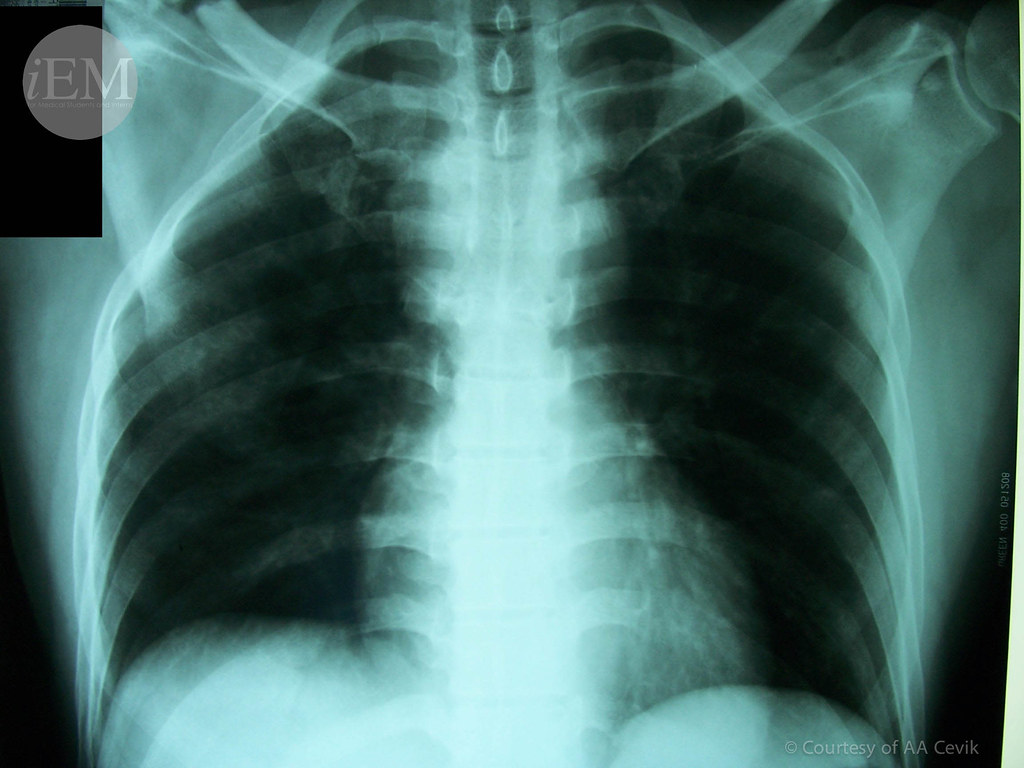

From www.flickr.com

8.1 Flail Chest Ribs Emergency Medicine Clinical Images and Videos Emt Flail Chest Treatment Also shown to reduce the need for tracheostomy,. This segment depresses inward during inspiration (due. Explore the critical aspects of emt management for chest injuries, including the diagnosis, treatment, and prehospital care strategies for conditions like pneumothorax, hemothorax,. Surgical repair of flail chest has been shown to reduce rates of pneumonia, permanent chest deformity, and mortality. Management of flail chest. Emt Flail Chest Treatment.